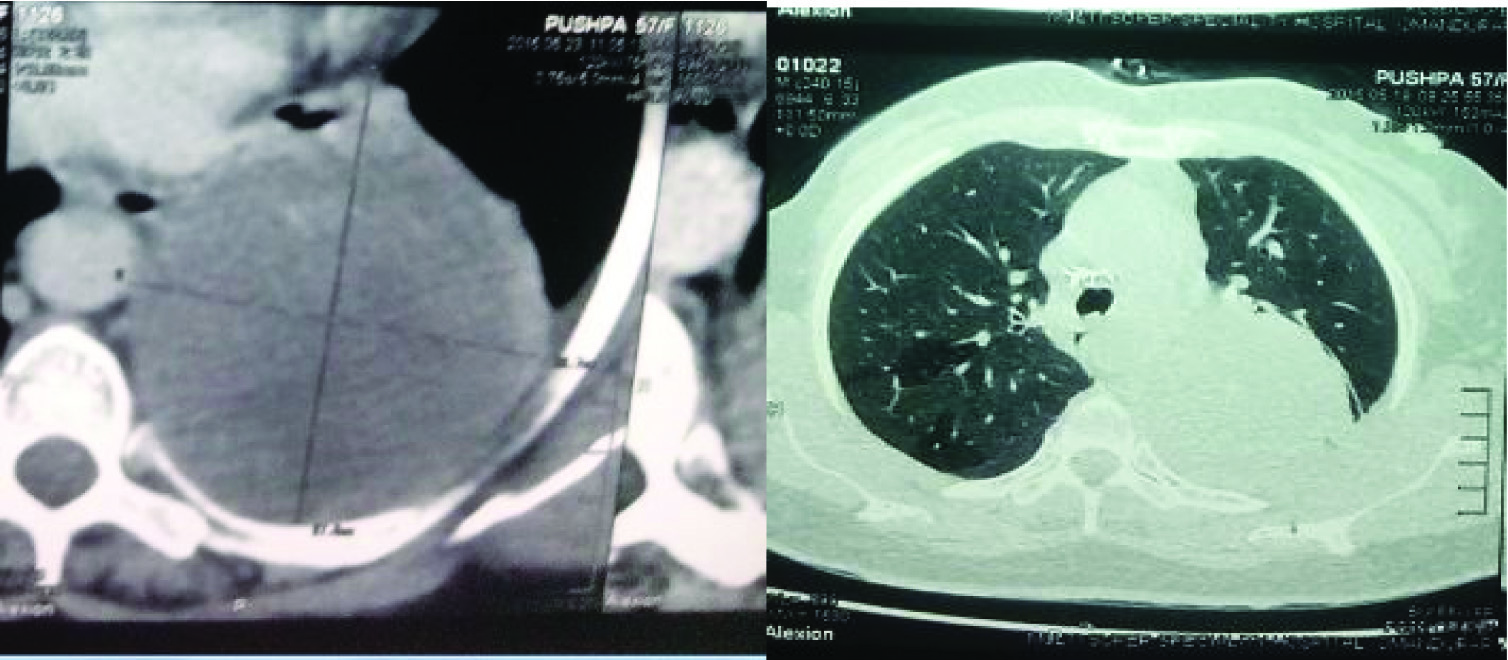

A 58-year-old post menopausal woman presented with complaints of dull aching pain in the posterior aspect of the chest wall for three months. Patient had past history of borderline phyllodes tumour of breast diagnosed on July 2009 and had undergone right mastectomy followed by chemotherapy and radiotherapy for which she was on follow-up till August 2013. Whole body bone scintigraphy done in August 2013 showed no evidence of bony metastasis. Patient was lost to follow up since then and was asymptomatic till three months before she reported to us. Chest X-ray [Table/Fig-1] revealed a well-defined homogenous opacity involving the left upper and mid zone. A small nodular opacity was noted in the right lower zone with absence of breast shadow. Computed Tomography thorax done revealed a large pleural based soft tissue density lesion extending from apicoposterior segment of the left upper lobe to superior basal segment of the left lower lobe [Table/Fig-2,3]. A nodule was also noted in the right lower lobe measuring 1.2 cm × 2.4 cm in the posterior basal segment of right lower lobe [Table/Fig-4]. Bronchoscopy revealed sluggish left vocal cord movements, distorted architecture of carina, and narrowed left upper lobe bronchus along with flattened and stretched bronchus of the lingular segment. The upper lobe bronchus could not be negotiated beyond the narrowing [Table/Fig-5,6]. All the above findings suggested the possibility of external compression of left upper lobe bronchus. Bronchoalveolar lavage sent for analysis revealed no evidence for malignancy or infection. Computed Tomography guided biopsy of the left sided mass lesion showed spindle cells with atypia in sheets and bundles on a myxoid stroma, delicate to broad collagen bundles with few dilated congested capillaries [Table/Fig-7]. No lung parenchyma was seen. Further immunohistochemistry staining was positive for vimentin, negative for ER (Estrogen Receptor), PR (progesterone receptor) & TTF (Thyroid transcription Factor). The Haematoxylin & Eosin staining, immunohistochemistry features were in favour of metastatic tumour. Clinical breast examination and mammography were normal. With the history of treated phyllodes tumour and confirmation by histopathological examination and immunohistochemistry we conclude that the mass present in the left side and the nodule of the right lower lobe as metastasis of the breast phyllodes tumour. After explaining the diagnosis and prognosis to the patient and their relatives, patient was started on chemotherapy under oncology care. Patient received six cycles of Paclitaxel, Epirubicin and cyclophosphamide with only partial response. Patient developed cardiac dysfunction, probably as a side effect of Epirubicin. So chemotherapy was withheld and patient is on symptomatic therapy at present.

CT-Thorax Lung window showing pleural based soft tissue density occupying the apicoposterior segment of the left upper lobe.

Nodule in right lower lobe measuring 1.2 × 2.4 cm in the posterior basal segment.